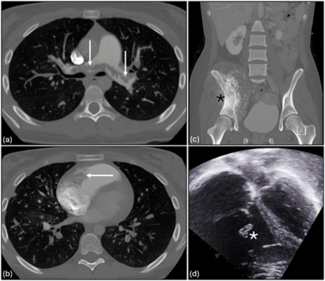

This case highlights the critical role of mechanical circulatory support in managing complex cardiopulmonary complications of metastatic malignancy.